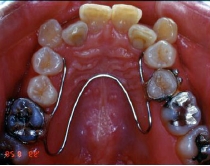

ポーター型拡大装置(緩徐拡大)

構造

リンガルアーチやナンスと同様にバンドと太めのワイヤー(0.8-1.0mm程度)を用いて、石膏模型上で製作します。

装置使用の目的

歯並び全体の横幅を広げるために用いる装置です。もっとも拡大が必要な位置に取り付けますので、装置の固定されている位置や形態はいろいろですが、装置の基本構造は同じで、写真のように歯の裏側に少し太めの針金をW型に沿わせ、奥歯に固定したバンドと一緒に一体化させて留めてあります。患者さんが自分で取り外すことはできませんが、調節が必要なときは先生が外して、調整後また留め直すという操作を繰り返していきます。